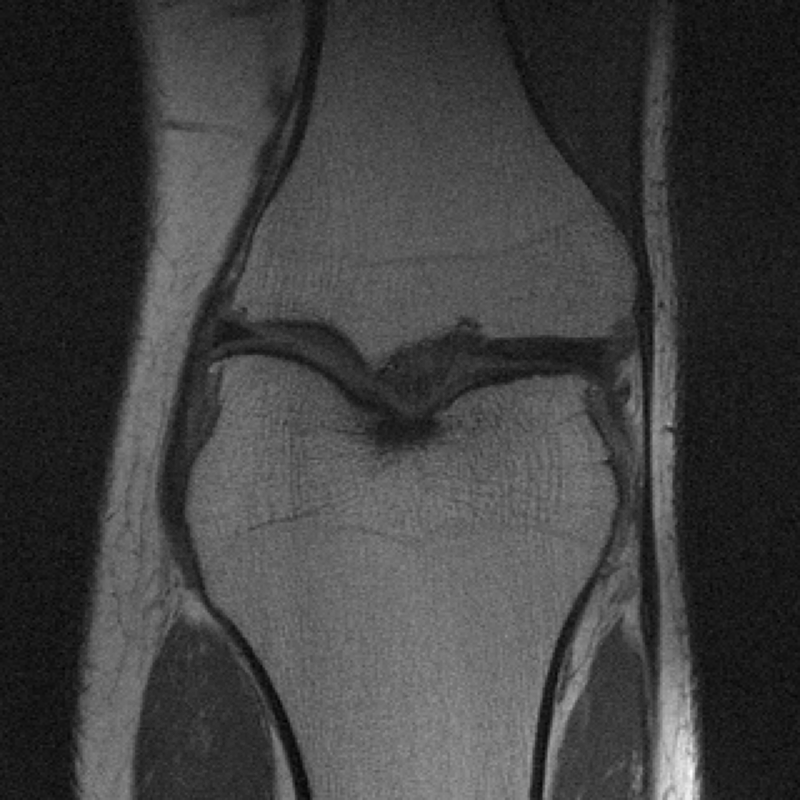

The data used in the undersampled MRI experiments were obtained from the NYU fastMRI Initiative [45]. The primary goal of the fastMRI dataset is to test whether machine learning can aid in the reconstruction of medical images. We trained and tested on a subset of the single-coil knee dataset, which consist of simulated single-coil measurements. In all tests, we use complex-valued data, which interfaces with our deep networks by treating the real and imaginary parts of the images as separate channels. We measure reconstruction accuracy with respect to the center 320320 pixels of the complex IFFT of the fully-sampled k-space data. For the purpose of visualization, we display only the magnitude images in the following sections.

In Table 1 we present our main results. We present sample reconstructions for the deblurring problem and MRI reconstruction problem in Figs. 7 and 8. For reference, the ground truth, inputs to the networks, a total variation regularized reconstruction, and a RED reconstruction are presented in Figs. 5 and 6. We also provide in the Appendix a table of SSIM values as well as the full version of Table 1, which contains the standard deviations of PSNR.

While the magnitude of the improvements vary across domains and problems, we find that retraining the network with the proposed model adaptation techniques significantly improve performance by several dBs in the new setting. This effect is particularly striking in the case of MRI reconstruction with MoDL, where the βnaiveβ approach of replacing with in the network gives catastrophic results (a roughly 9 dB drop in reconstruction PSNR), while the proposed model adaptation approaches give reconstruction PSNRs within 1-2 dB of the baseline approach of training and testing with the same forward model in the case where is known.